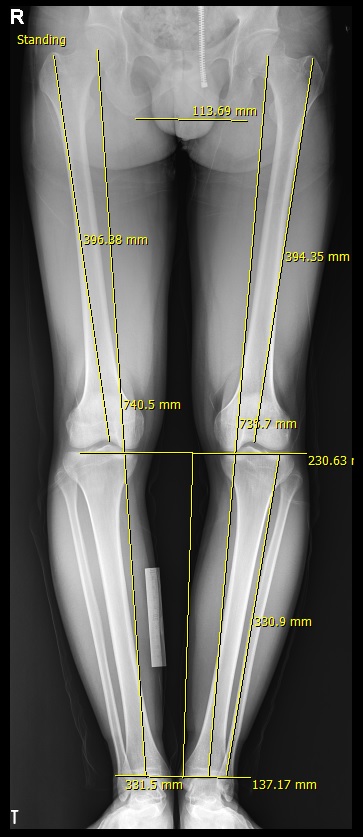

아래 사진을 보면, 수술전 종아리의 길이는 실제로 331mm로 측정되는데, 이는 영상 보정을 옆의 금속자 10cm를 기준으로 보정한 상태이며, 수술 후 종아리의 길이는 실제로 395mm로 64mm의 연장이 된 상태이다. 수술 후 사진에서 10cm 금속자를 이용해서 보정한 사진이다. 실제 이 환자의 척추 사진인데 측만증이 흉요추부에 있어 키 측정에서 오차를 나타낼 수 있다.

종아리 속성 연장 수술 환자의 수술 전후 엑스레이 사진으로 종아리 길이가 영상 보정 후 331mm에서 395mm로 측정된다. 64mm 연장 사진으로 6.4cm 연장된 사진이며, 이는 실측과 오차가 없다고 생각할 수 있다.